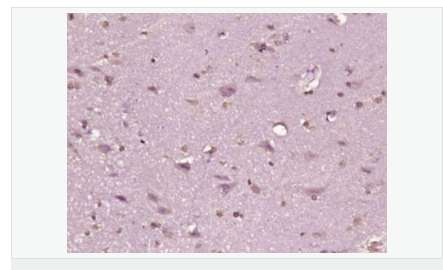

| 產品應用 | WB=1:500-2000 ELISA=1:5000-10000 IHC-P=1:100-500 IHC-F=1:100-500 Flow-Cyt=0.2μg /test IF=1:100-500 (石蠟切片需做抗原修復) not yet tested in other applications. optimal dilutions/concentrations should be determined by the end user. |